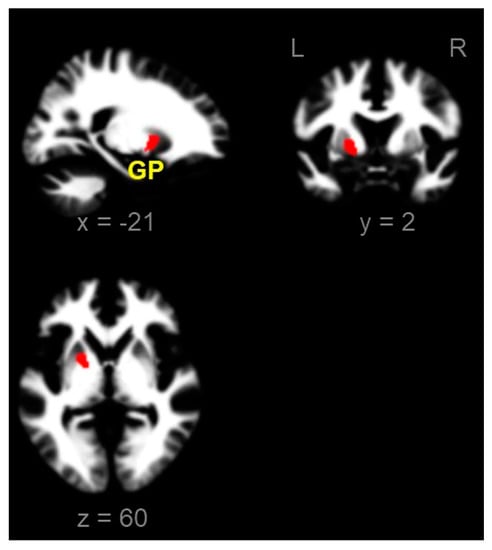

There was no significant difference in the GM between the two groups. In the WM, ADPs showed reduced volumes in the GP (two-sample t-test, p-FWE < 0.05, and cluster size > 100 voxel)s (Figure 2).

Figure 2.

Reduced local white matter volumes in alcohol-dependent patients compared with those in healthy controls (two sample t-test, p-FWE < 0.05, and cluster size > 100 voxels). L, left; R, right; GP, globus pallidus (x, y, z = −21, 2, 0); FWE, family-wise error.